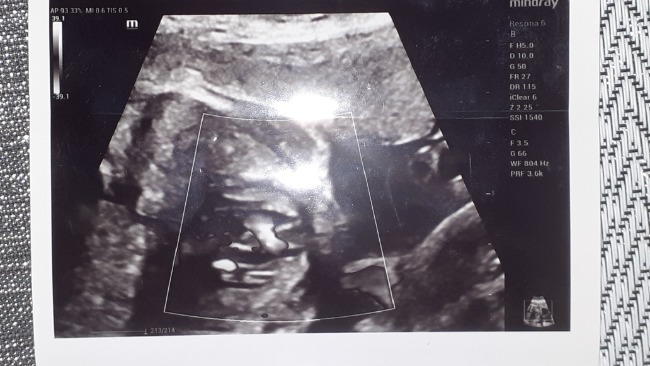

pomagam.pl/a7a98y💛💛💛 Drodzy Ludzie - Dobrego, Wielkiego, Pomocnego Serca. ❤ Zwracam się do Was z Ogromną Prośbą🙏 🙏🙏o Pomoc w Uratowaniu Mojego Nienarodzonego jeszcze Synka, który już teraz w brzuszku ma wadę Serduszka. 💔💔Mam na imię Natalia. Jestem teraz samotną matką, którą zostawił ojciec dziecka jak się dowiedział że jestem w ciąży. Kazał usunąć ciążę😭🥺Rodziny nie mamy. Rodzice już nie żyją 😥 i zostalam sama z Synkiem na tym świecie. Pracowałam aż do 6 tego miesiąca będąc w ciąży. Na badaniu USG oraz Prenatalnym dowiedziałam się że Synek ma wadę Serduszka 💔💔i po porodzie będzie konieczny zabieg lub operacja.😭😭 Zostało nam bardzo mało czasu do porodu. Termin porodu mam wyznaczony na 26 września. Zebrane pieniążki bęndow przeznaczone na ratowanie i koszty leczenia mojego Synka. Wszystkie badania, wizyty, paragony, koszty lekarstw z apteki będę udostępniać na stronie. Liczy się każda złotówka. Z góry Dziękuję Wam Ludzie Dobrego Serca❤ za każdą wpłaconą kwotę. Z całego Serca ❤❤Mojego i Synka życzę Wam Zdrowia - bo Ono jest w życiu najważniejsze. ❤❤❤🙏🙏🙏 pomagam.pl/a7a98y‼‼